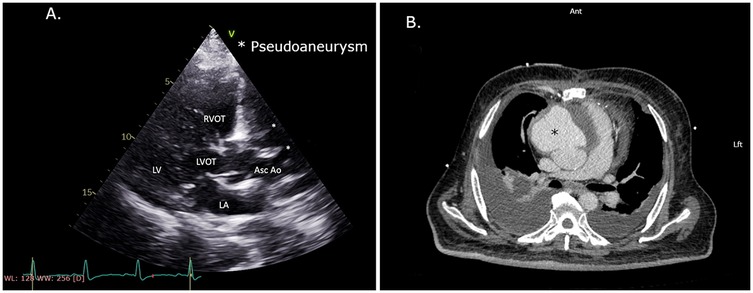

Continued improvement allowed extubation a few hours later. Postoperative complications included right transudative pleural effusion, which required placement of a chest tube, and acute kidney injury with oliguria and creatinine up to 2.7 mg/dl. During the following days, kidney function rapidly improved back to baseline, allowing the performance of triphasic CTA. This demonstrated no endoleak but showed a large hematoma pressing on the heart in the anterior mediastinum (Figure 3A). Repeated TEE still showed restrictive cardiac physiology.

Figure 3

CT scans of the chest area after pseudoaneurysm endovascular repair. Panel A shows a cross-sectional view with a marked circular area indicating a large clot mass. Panel B presents a similar view after surgical removal of the mass.

Figure 3. (A) CTA scan after endovascular pseudoaneurysm repair showing a large anterior mass. (B) CTA scan after endovascular pseudoaneurysm repair and hemisternotomy to remove blood clot and patch the aorta. CTA, computed tomography angiography.

A second multidisciplinary heart team evaluation concluded that further intervention is needed to relieve the mediastinal pressure created by the remaining hematoma. As the patient was now stable to allow surgical intervention, a limited upper hemisternotomy (third intercostal space) was performed. The anterior mediastinum was cleared of blood clots (Figure 4) and the ascending aorta was exposed. The surgical team examined the stent graft confirming its position approximately 2 cm above the STJ. A small bleeding source was noticed from the lower end of the aortic opening. A bovine pericardial patch was mounted with bio-glue and manual pressure was placed on the patch for 5 min to ensure adequate patch alignment. Hemodynamic improvement was demonstrated, with rapid postoperative decline in central venous pressure from 23 to 13 mmHg. It should be noted that cultures from clots removed during the surgery and blood cultures taken during hospitalization were all negative.

The patient was extubated a few hours later, and chest tubes were removed. Follow-up CTA showed a reduced mediastinal mass with no apparent contrast extravasation from the covered stent (Figure 3B). The patient was discharged home 3 weeks after admission with preserved left and right ventricular function and a return to baseline kidney function. The patient was discharged with supplemental oxygen therapy due to atelectasis. The patient returned for routine follow-up visits at 2, 6, and 12 months postoperatively. He is currently feeling well and continues follow-ups through his primary care physician.